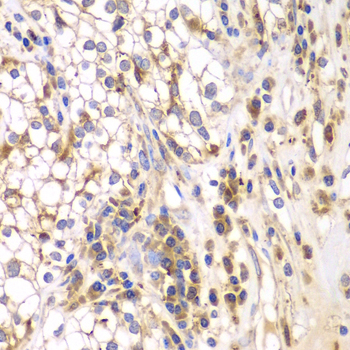

Immunohistochemistry of paraffin-embedded human kidney cancer using SRPK1 antibody at dilution of 1:200 (400x lens).